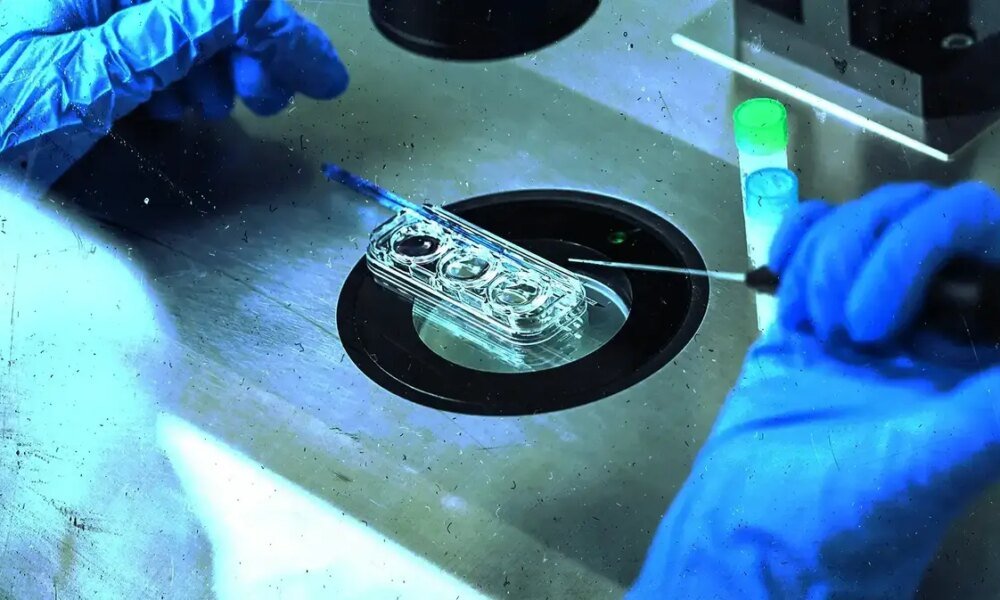

מרכז הפוריות בניוקאסל מדווח כי 22 משפחות עברו את התהליך, ונולדו ממנו ארבעה בנים וארבע בנות (כולל זוג תאומים), וכן הריון אחד נוסף שמתקיים כעת. אף...